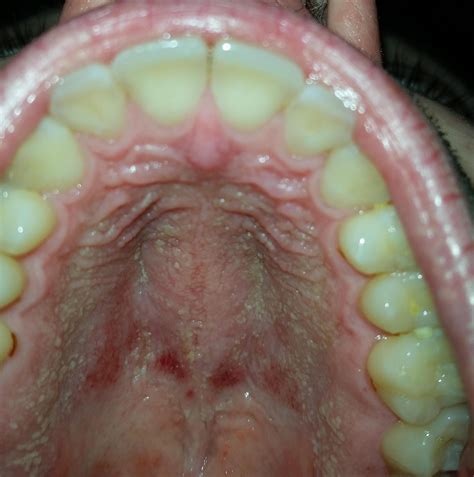

Oral Pruritus Causes Intense Itching Inside Your Mouth